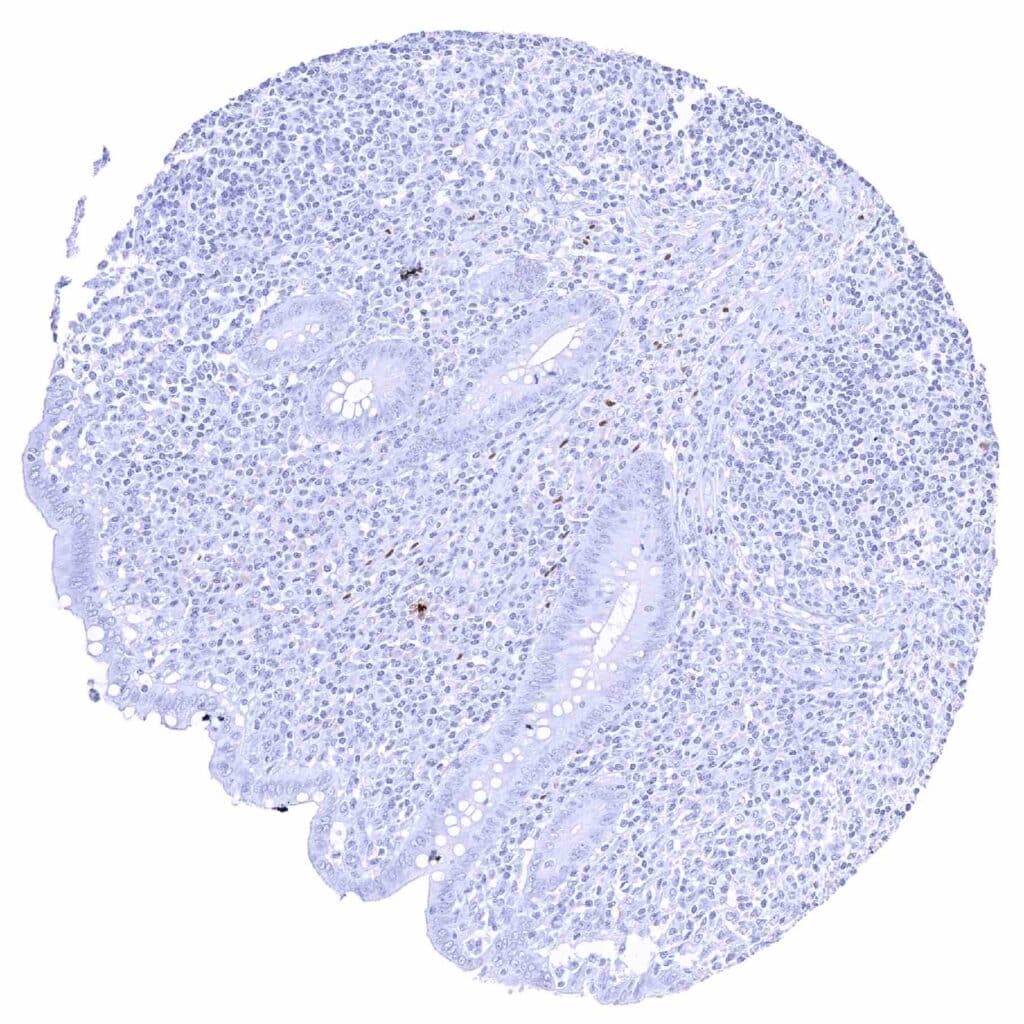

Thymus